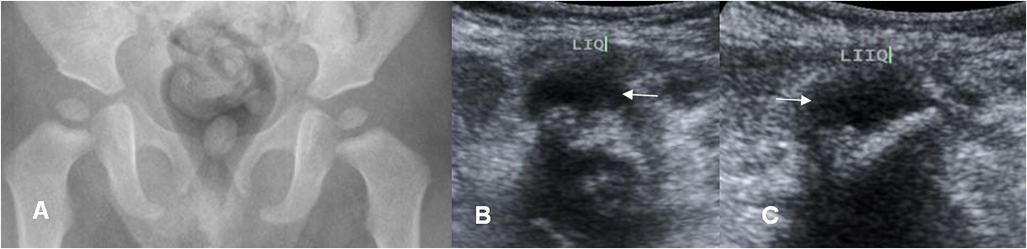

Fig 142 C. Artritis séptica.

A: Rx AP. No se encuentra anormalidades.

B: Ecografía transversal y C: Ecografía longitudinal. Escasa cantidad de derrame articular izquierdo. Después se puncionó y cultivó Estafilococo, por artritis séptica.